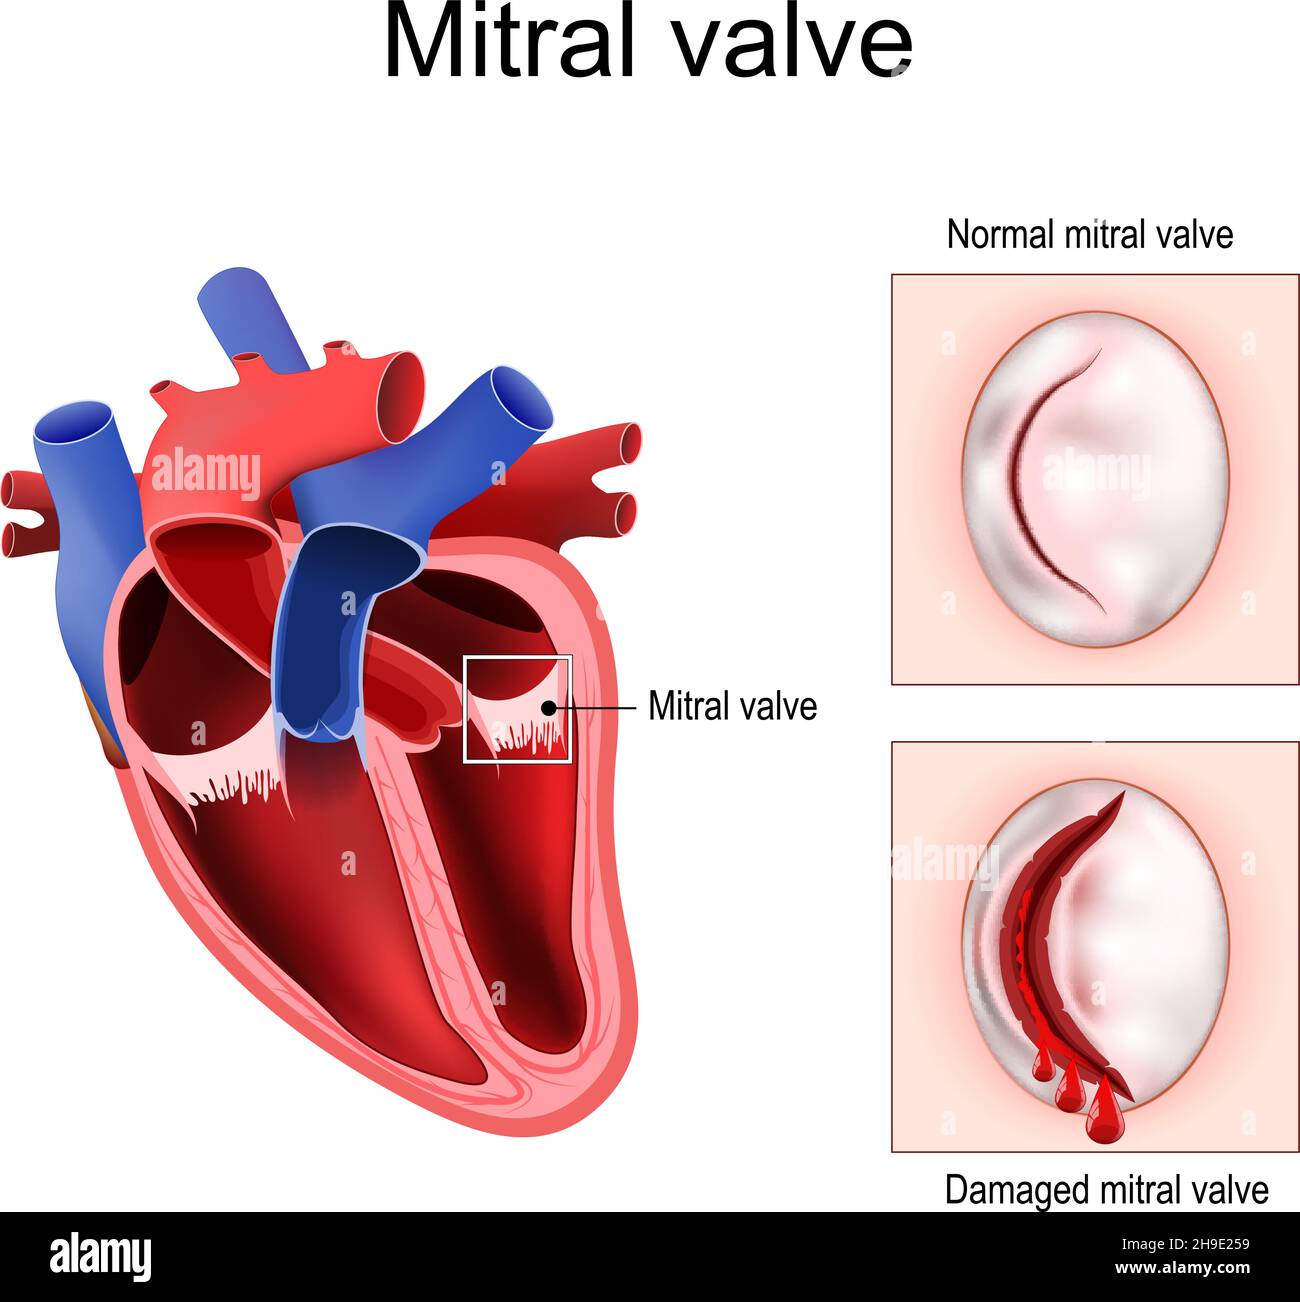

Heart anatomy. Close-up of Normal Mitral valve and Damaged mitral valve. Cross section of human heart. detailed diagram. Vector poster Stock Vectorhttps://www.alamy.com/image-license-details/?v=1https://www.alamy.com/heart-anatomy-close-up-of-normal-mitral-valve-and-damaged-mitral-valve-cross-section-of-human-heart-detailed-diagram-vector-poster-image453310517.html

Heart anatomy. Close-up of Normal Mitral valve and Damaged mitral valve. Cross section of human heart. detailed diagram. Vector poster Stock Vectorhttps://www.alamy.com/image-license-details/?v=1https://www.alamy.com/heart-anatomy-close-up-of-normal-mitral-valve-and-damaged-mitral-valve-cross-section-of-human-heart-detailed-diagram-vector-poster-image453310517.htmlRF2H9E259–Heart anatomy. Close-up of Normal Mitral valve and Damaged mitral valve. Cross section of human heart. detailed diagram. Vector poster